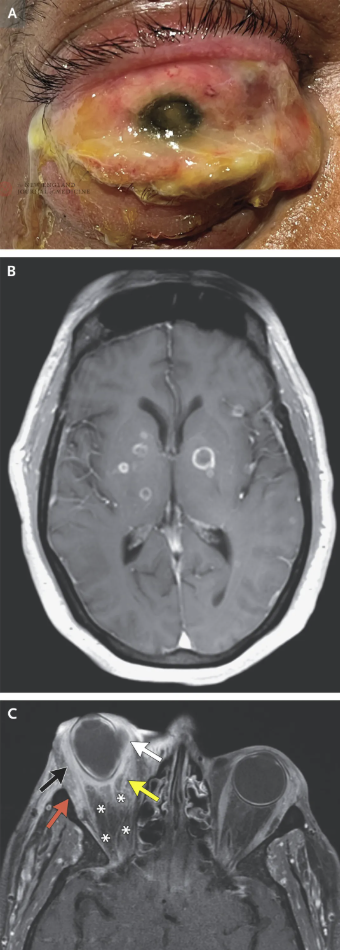

本例具备多个暴发性细菌性眼内炎的临床与影像学特征。此病多见于眼压升高时,角膜因内皮泵功能受损而出现水肿。裂隙灯检查几乎总可见前房内大量白细胞,部分病例出现前房积脓(即“脓层”,图2)。虽然本例未观察到典型脓层,但前房中存在致密纤维蛋白沉积——尽管少见,已有文献报道肺炎克雷伯菌所致内源性眼内炎可表现出此特征。

图2. 眼解剖及眼内炎

此外,玻璃体炎是眼内炎的另一常见表现。由于患者右眼玻璃体无法直接观察,改行B超检查,结果显示玻璃体混浊,进一步支持眼内炎诊断。B超所见高回声性视网膜下物质,可能为视网膜下脓肿。

内源性细菌性眼内炎是一种临床诊断,需结合血培养证实菌血症,部分病例还需玻璃体或房水培养阳性(图2)。该病最常见的原发感染灶包括:感染性心内膜炎、尿路感染、胃肠道手术后感染,以及肺炎克雷伯菌引起的肝脓肿等。